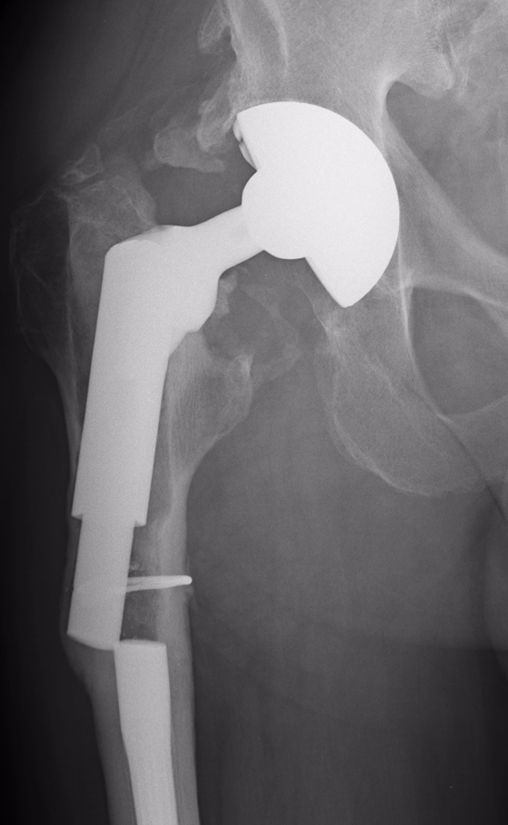

Below are the prostheses with links we commonly use but this is not exhaustive.